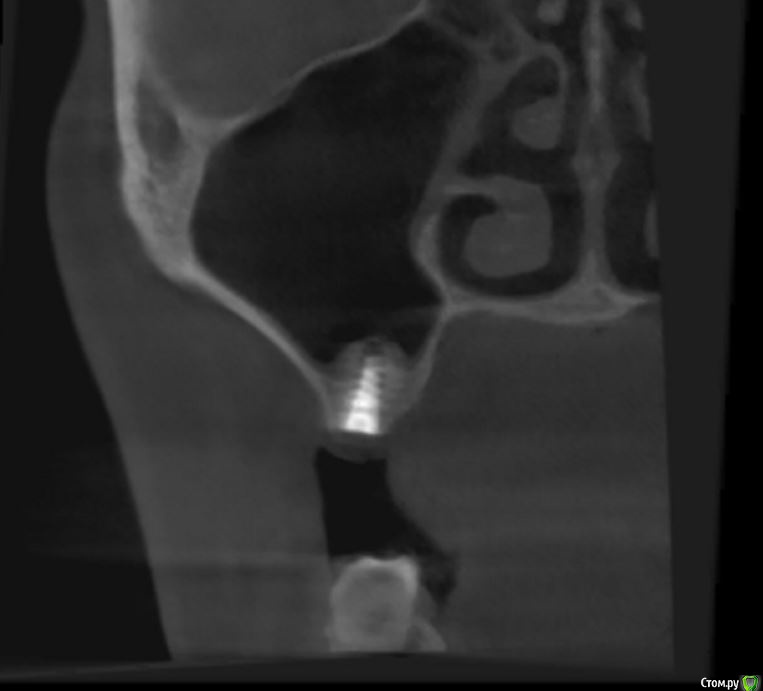

jm3300 Опубликовано 12 июля, 2016 Автор Поделиться Опубликовано 12 июля, 2016 А до операции КТ могли бы выложить? И сколько времени отсутствовали зубы в этой области?отсутствовали достаточно долги. КТ до: Ссылка на комментарий

jm3300 Опубликовано 14 июля, 2016 Автор Поделиться Опубликовано 14 июля, 2016 выкладываю кт Ссылка на комментарий

умножающий печаль Опубликовано 14 июля, 2016 Поделиться Опубликовано 14 июля, 2016 Промыть пазуху через соустье, курсом. Я отправляю к ЛОРам. Антибиотикотерапия, гипосенсибилизация. Один из винтов вестибулярно без костной поддержки, на мой взгляд. 1 Ссылка на комментарий

red_butler Опубликовано 15 июля, 2016 Поделиться Опубликовано 15 июля, 2016 гайморит всё таки есть?Не увидел, один винт похоже на выход 1 Ссылка на комментарий

red_butler Опубликовано 15 июля, 2016 Поделиться Опубликовано 15 июля, 2016 Пазуха чистая, Антон, какой винт на выход не понял?Может у пац аллергия ?На последних срезах, вестибулярно на 2/3 кости нет.Какая уж аллергия, если боль и отек 1 Ссылка на комментарий

умножающий печаль Опубликовано 15 июля, 2016 Поделиться Опубликовано 15 июля, 2016 Тоже не понял, вроде все хорошо стоят. Главное слизистые то в покое.Это пока в покое. Винт не покрытый костью, долго под мягкими тканями оставаться не будет. Неизбежна рецессия со всеми вытекающими. 1 Ссылка на комментарий